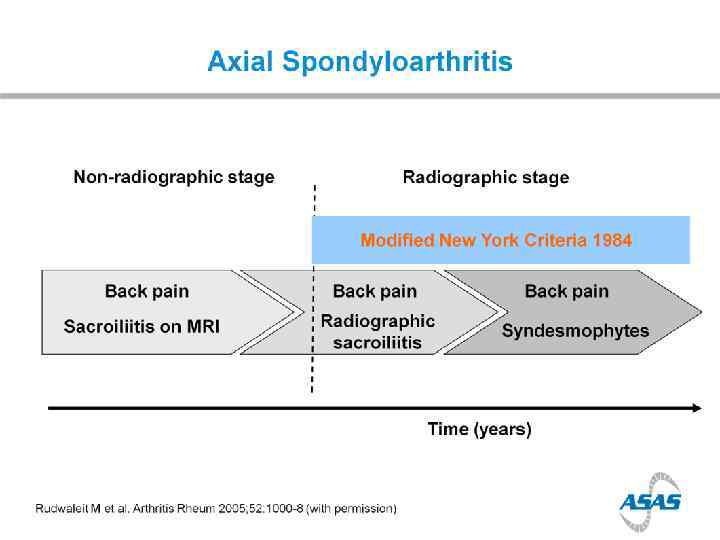

Prevalence of Axial Sp. A in US (NHANES study) chronic back pain in 20% of population IBP in 7% of population; > in younger adults Ax. Sp. A (including AS) in 1. 4% AS in 0. 5% AS nr. Ax. Sp. A MALES=FEMALES (Ax. Sp. A); M: F=2: 1 (AS) 12% in 2 years

Disease progression

Disease progression > in males > in smokers > in those with high CRP >>> in those with syndesmophytes at baseline